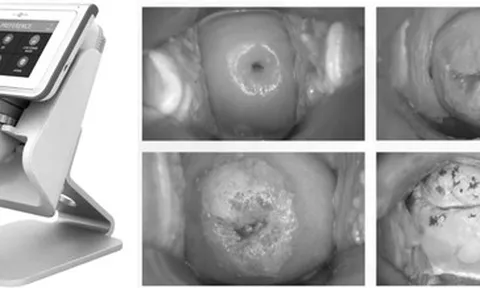

Bệnh viện sản khoa ở TP HCM dùng AI chẩn đoán sớm ung thư cổ tử cung

(NLĐO) - Hệ thống này có hơn 100.000 hình ảnh dữ liệu về cổ tử cung, giúp sớm phát hiện bệnh, đồng thời mở ra hướng mới cho ngành sản phụ khoa.